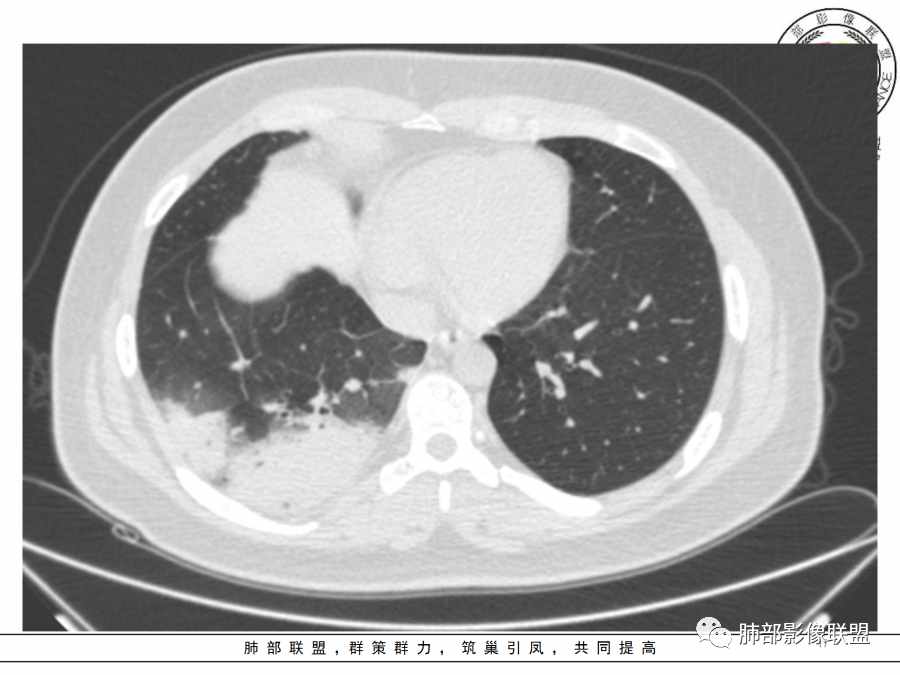

右肺胸膜下实变,病变跨多个叶生长,宽基底与胸膜相连,近端支气管穿行病灶内,并可见片状磨玻璃影,边界清,部分远端小支气管堵塞,支气管略有扩张,周围散发小结节,临床年轻女性,炎性指标高,发热六日,首先考虑感染性病变(肺链,奴卡,隐球,OP)鉴别淋巴瘤。

年轻女性,无明显诱因发热,体温略高,起病较急,有畏寒,右下肺紧贴胸膜下片状实变影,部分融合,外围有结节影,性质比较单一,类似于蘑菇兄弟,病灶周围伴有晕,支气管进入近端扩张远端堵塞,常规考虑感染,肺炎链球菌、隐球菌。

青年女性,发热咳嗽5天,炎症标志物升高。右肺下叶大片实变伴周围GGO,GGO内未见细网格,主体与胸膜平行,似多个病灶融合,实变区内见支气管部分进入,部分支气管受压狭窄,周围可见多发卫星病灶。支持炎性,考虑隐球感染,鉴别op。

年轻女性,急性起病,咳嗽,发热,黄痰,白细胞高,CRP基本正常,基础体健。CT提示右肺下叶实变,宽基底与胸膜相连,长轴平行于胸膜,可见支气管充气征,于病变中央截断,走形自然,胸膜下脂肪间隙可见,倾向于隐球菌,鉴别肺链,军团菌等。

年轻患者,右肺下叶大片状实变影,长轴与胸膜平行,内见含气支气管征,周围磨玻璃晕影。考虑感染性病变,隐球?

病灶长轴与胸膜平行,边缘有晕,病灶融合趋势,支气管进入,走行自如,考虑隐球菌肺炎。

年轻女性,急性发病,咳嗽咳痰五天,炎性指标升高,右肺下叶胸膜下大片实变影,周围见磨玻璃影,边界清晰,长轴与胸膜平行,呈融合趋势,支气管进入走行自然,远端截断,考虑炎性,隐球菌可能。

年轻女性,发热,急性发病,白细胞高,右肺下叶大片实变,长轴与胸膜平行,内见支气管走行,远端截断,周围有晕,晕边界清,考虑感染,隐球可能,鉴别淋巴瘤。

年轻女性,右肺下叶胸膜下多发实变、结节影,宽基底与胸膜相连,边缘模糊不清,实变内见支气管穿行,血象高,考虑感染性病变,大叶性肺炎?隐球?

青年女性,发热咳嗽急性起病,右肺下叶大片状实变密度影,长轴平行于胸膜,边缘模糊可见磨玻璃影及高密度结节影,实变内可见支气管穿行,直达病灶远端,考虑感染性病变,隐球菌可能大。

右肺胸膜下实变,病变跨多个叶生长,相互融合,宽基底与胸膜相连,支气管气象,并可见片状磨玻璃影,边界清,炎性指标高,发热六日,考虑感染病变,链球菌?腺病毒待排。

右肺下叶大片状实变影,长轴平行于胸膜,边缘模糊可见磨玻璃影,支气管进入,部分近端阻塞,考虑感染性病变,隐球菌,鉴别大叶性肺炎。

年轻女性,起病急,白细胞,C反高,存在感染。右下肺大片实变影,支气管充气征,长轴平行胸膜,似多个病灶融合,周围GGO,部分清,部分不清。考虑感染,隐球可能。

青年人,右肺多发团片状阴影,边缘模糊,周围可见磨玻璃影,内部有支气管空气征,考虑感染性病变,隐球菌感染可能。

右肺下叶大片状实变影,从外向内,长轴平行于胸膜,边缘模糊,可见磨玻璃影,支气管进入,远端部分阻塞,考虑感染性病变,隐球菌,鉴别淋巴瘤。

26岁,女性,发热、咳嗽5天。咳少量黄痰,起病急,病程短,白细胞及中性高,血沉及D-二聚体增高。胸部CT:右肺下叶大片实变,长轴沿胸膜分布,宽基底与胸膜接触,边界不清,周围GGO,部分团片影融合,病灶内可见支气管充气征,部分支气管进入病灶后阻塞。考虑:感染性病变,隐球菌?脓毒肺栓塞?鉴别:肺炎型肺Ca。

年轻女性,右肺下叶一大片实变影,似有多个结节影融合,周围有晕,内见支气管充气征,部分支气管进入后截断,病变近胸膜,长轴胸膜平行,考虑炎性,隐球菌首先考虑。

青年女性,影像表现右肺下叶胸膜下大片状实变影,近端见充气支气管征,边缘见片状磨玻璃影,下叶背段尚可见一结节。考虑感染性病变,隐球菌感染可能。

右下肺大片实变影,空气支气管征,边缘GGO,小叶间隔增厚,周围有蘑菇兄弟,基底宽,与胸膜平行,考虑隐球菌感染,鉴别肺炎型肺癌。

晨读:年轻女性,右肺胸膜下实变影,平行于胸膜,边缘磨玻璃影,内见支气管充气征,走形自然,略扩张。考虑感染性改变,隐球,肺链。2月发病,病毒性肺炎要考虑。鉴别淋巴瘤。

晨读:年轻女性,发热咳嗽5天。白细胞计数升高。右肺下叶大片状高密度影,边缘模糊,有实变 GGO,其内见支气管气相、无受压变细,无枯枝表现,其近端支气管无异常,右肺下叶背段见结节状影,定性考虑:炎症,隐球菌感染可能,炎症型肺癌不支持。

右下肺胸膜下大片状高密度影,其长轴与胸膜平行,病灶近端GGO模糊,部分支气管进入后阻断,支持感染性病变,考虑隐球菌